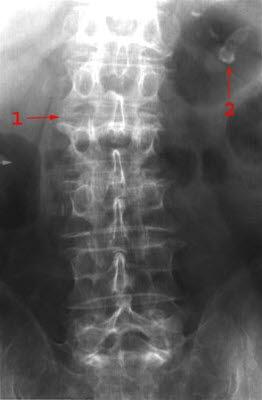

Ulike bruddtyper

Ulike bruddtyper kan oppstå:

- Kompresjonsbrudd

- Betyr at selve virvelen er blitt presset sammen i lengderetningen (se illustrasjonene over). En bruddtype som er vanlig ved beinskjørhet, og som vanligvis er et stabilt brudd.

Røntgen kan avklare diagnosen. Ved mistanke om instabilitet og ved nakkeskader tas CT. MR tas kun ved behov for bedre bilder av ryggmargen og leddbånd.